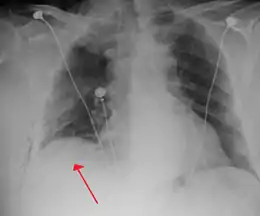

Chest X-ray

A plain chest radiograph, ideally with the X-ray beams being projected from the back (posteroanterior, or "PA"), and during maximal inspiration (holding one's breath), is the most appropriate first investigation.[30] It is not believed that routinely taking images during expiration would confer any benefit.[31] Still, they may be useful in the detection of a pneumothorax when clinical suspicion is high but yet an inspiratory radiograph appears normal.[32] Also, if the PA X-ray does not show a pneumothorax but there is a strong suspicion of one, lateral X-rays (with beams projecting from the side) may be performed, but this is not routine practice.[15][19]

Anteroposterior inspired X-ray, showing subtle left-sided pneumothorax caused by port insertion

Lateral inspired X-ray at the same time, more clearly showing the pneumothorax posteriorly in this case

Anteroposterior expired X-ray at the same time, more clearly showing the pneumothorax in this case

Chest X-ray showing a pneumothorax on the right (left in the image), where the absence of lung markings indicates that there is free air inside the chest

Chest X-ray showing the features of pneumothorax on the left side of the person (right in image)